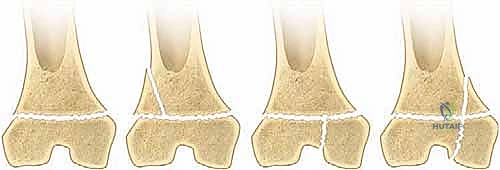

تصنيف كسور صفيحة النمو: نظام سالتر-هاريس (Salter-Harris)

لغة التخاطب بين أطباء جراحة العظام حول العالم تعتمد على نظام تصنيف "سالتر-هاريس". هذا التصنيف لا يصف شكل الكسر فحسب، بل يرشد الأستاذ الدكتور محمد هطيف في تحديد استراتيجية العلاج الدقيقة وتوقع النتائج المستقبلية لنمو الطفل.

ينقسم هذا التصنيف إلى خمسة أنواع رئيسية، وسنشرحها هنا بالتفصيل المطبق على عظم الفخذ البعيد:

النوع الأول (Type I) والنوع الثاني (Type II): الكسور خارج المفصل

هذه كسور انفصالية تحدث خارج نطاق السطح المفصلي للركبة.

* النوع الأول (I): يمر الكسر أفقياً بالكامل عبر طبقة الخلايا المتضخمة في صفيحة النمو، مما يفصل المشاشة عن الكردوس دون كسر العظم نفسه. قد لا يظهر في الأشعة السينية بوضوح إذا لم يحدث انزياح.

* النوع الثاني (II): هو الأكثر شيوعاً. يمر الكسر عبر صفيحة النمو ثم ينحرف صعوداً ليكسر جزءاً مثلثاً من عظم الكردوس. هذه القطعة العظمية المثلثة تُعرف طبياً باسم "شظية ثورستون-هولاند" (Thurston-Holland fragment).

* التوقعات: على الرغم من أن هذه الأنواع عادة ما يكون لها تشخيص أفضل للنمو مقارنة بالأنواع الأخرى، إلا أن كسور الفخذ البعيدة تحديداً تكون أكثر عرضة لاضطرابات النمو (بنسبة تصل إلى 40%) مقارنة بإصابات صفيحة النمو في أماكن أخرى من الجسم (مثل المعصم)، وذلك بسبب الشكل المتموج المعقد للصفيحة الفخذية.

النوع الثالث (Type III) والنوع الرابع (Type IV): الكسور داخل المفصل

هذه الكسور أكثر خطورة لأنها تخترق سطح المفصل وتدمر طبقات الخلايا الجذعية في صفيحة النمو.

* النوع الثالث (III): يبدأ الكسر من داخل المفصل، يمر عبر المشاشة (Epiphysis)، ثم يمتد أفقياً عبر صفيحة النمو.

* النوع الرابع (IV): كسر عمودي خطير. يمتد من السطح المفصلي للركبة، صعوداً عبر المشاشة، مخترقاً صفيحة النمو بالكامل، ومستمراً إلى داخل عظم الكردوس.

* التوقعات: تحمل هذه الإصابات داخل المفصل خطراً عالياً جداً لاضطرابات النمو، وتكوين جسور عظمية غير طبيعية (Physeal Bars)، وعدم تطابق الأسطح المفصلية (مما يؤدي لالتهاب المفاصل المبكر). تستدعي هذه الحالات تدخلاً جراحياً دقيقاً لإعادة العظم إلى وضعه التشريحي بدقة متناهية.

النوع الخامس (Type V): كسر الانضغاط (السحق)

نادر الحدوث ولكنه الأسوأ على الإطلاق. يحدث نتيجة قوة ضغط هائلة (مثل السقوط من ارتفاع شاهق) تؤدي إلى سحق صفيحة النمو وتدمير خلاياها دون وجود خط كسر واضح في العظم. للأسف، غالباً ما يتم تشخيصه متأخراً عندما يلاحظ الأهل توقف نمو ساق الطفل.